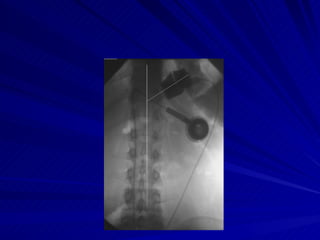

Copyright © 2006 by the American Roentgen Ray Society Mortele, K. J. et al. Am. J. Roentgenol. 2001;177:77-84 -- Misplaced band in 45-year-old woman presenting with severe vomiting

Concentric pouch dilatation because of a narrow stoma . .  Contrast material enters  the gastric fundus ( F ).  Dilated pouch  ( P ), narrow stoma